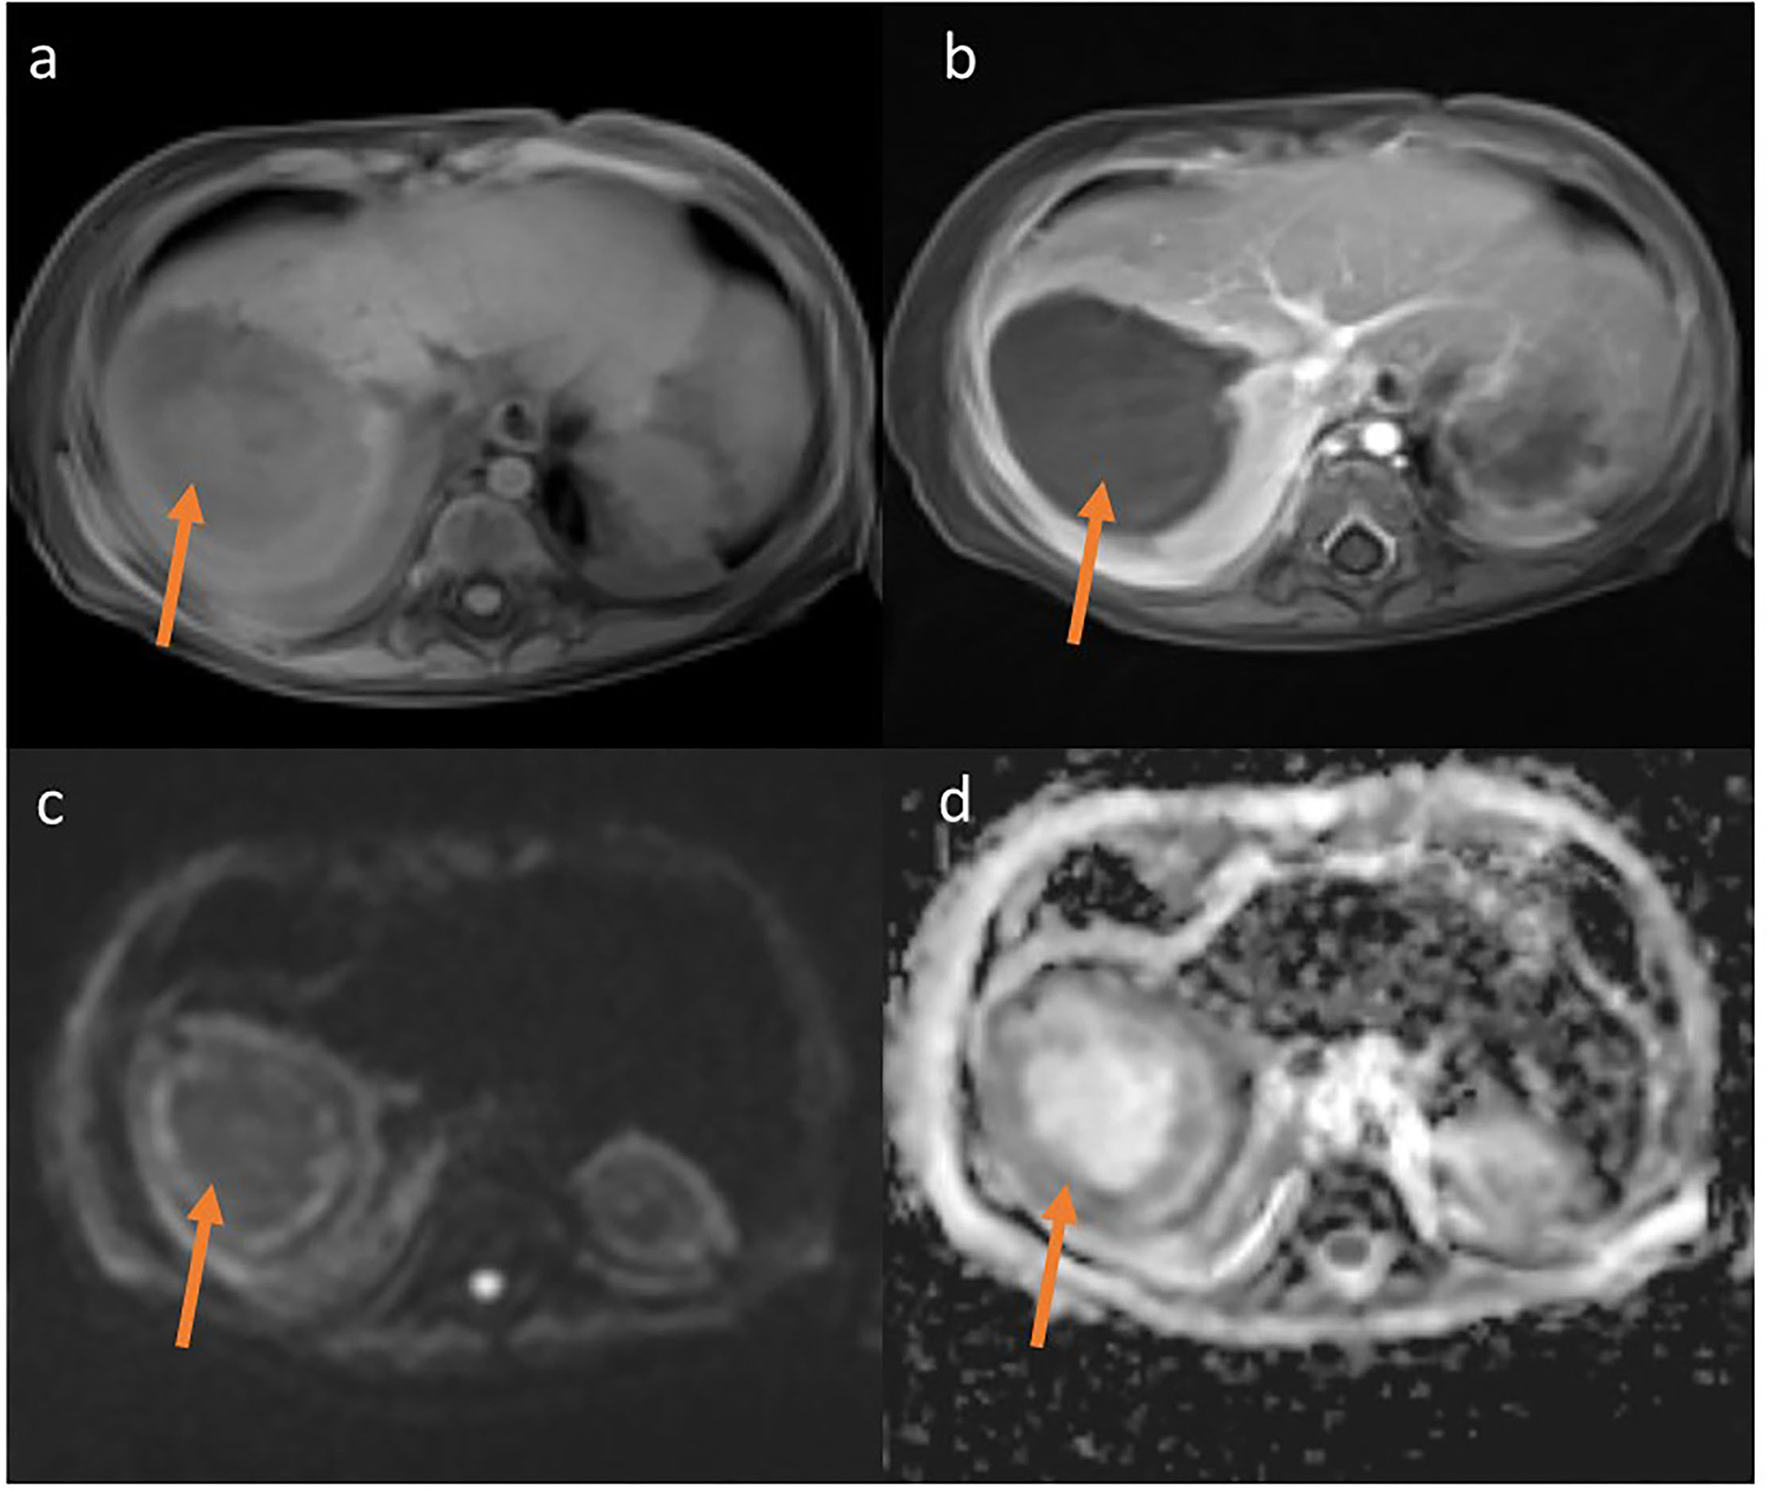

Treatment in the first week was complicated by rotavirus infection. During the second week of hospitalization, a perianal abscess appeared, and after a further 5 days, the child began to have a fever, the liver enlarged by 3 cm. Ultrasonography and magnetic resonance imaging (MRI) (Figures 2, 3) revealed a well-demarcated, hypoechoic area in segment VII of the liver.

Figure 3

MRT T1-weighted Starvibe FS, hipointense lesions in right lobe of liver (a) T1-weighted Starvibe FS post contrast-nonenhancing lesion (b), DWI b800 (c) ADC (d)-peripheral diffusion restriction (examination performed before surgery).

The lesion measured 32 x 27 mm, with no detectable vascular flow on CD or SMI. A similar lesion was located at the border of segments VI and VII (16 x 17 mm, border 4 mm) and two other adjacent lesions in segment V (or one hourglass-shaped) measuring 17 x 17 mm and 12 x 9 mm. Additionally, an irregular, extensive parenchymal area with increased echogenicity was observed at the border of segments VI and VII. The ultrasound image of the lesions indicated multiple liver abscesses. In the subcutaneous tissue of the rectal region on both sides, hyperechoic areas surrounded by a hypoechoic “halo” with strongly increased vascular flow registered in SMI examination were observed (features of inflammation). The lesion on the right side measured 8.5 x 2.5 x 19 mm, on the left 7.5 x 2.5 x 18 mm.

Despite the amphotericin B liposomal treatment further progression of the fungal infection was observed. The child developed massive bleeding from the upper small intestine due to infiltration of the intestinal wall by the fungus. The girl underwent repeated gastroscopy and colonoscopy, pleural drainage was necessary. Two exploratory laparotomies had to be performed, during which a significant amount of blood was found inside the small intestine, but no specific bleeding site was identified. The child's condition slowly improved, and the use of a combination of antifungal treatment with two drugs isavuconazole and amphotericin B liposomal resulted in absorption of the perianal abscess and reduction of the liver abscesses. It also allowed the leukemia to be treated by day 100 of the protocol and achieve cytological and molecular remission on 33rd day of the protocol. Five months after admission, another laparotomy was performed, during which the lesions–liver abscesses, were finally radically removed. They were hard, consolidated and markedly limited. One of the lesions infiltrated the diaphragm, so a fragment of the diaphragm must be removed. Above the diaphragm, an inflammatory changed, fibrotic lung was visualized, which was also resected. The histopathological examination of the removed lesions as well as culture confirmed Rhizopus microspores. The detailed treatment plan, examinations and procedures performed are shown in Figure 5.